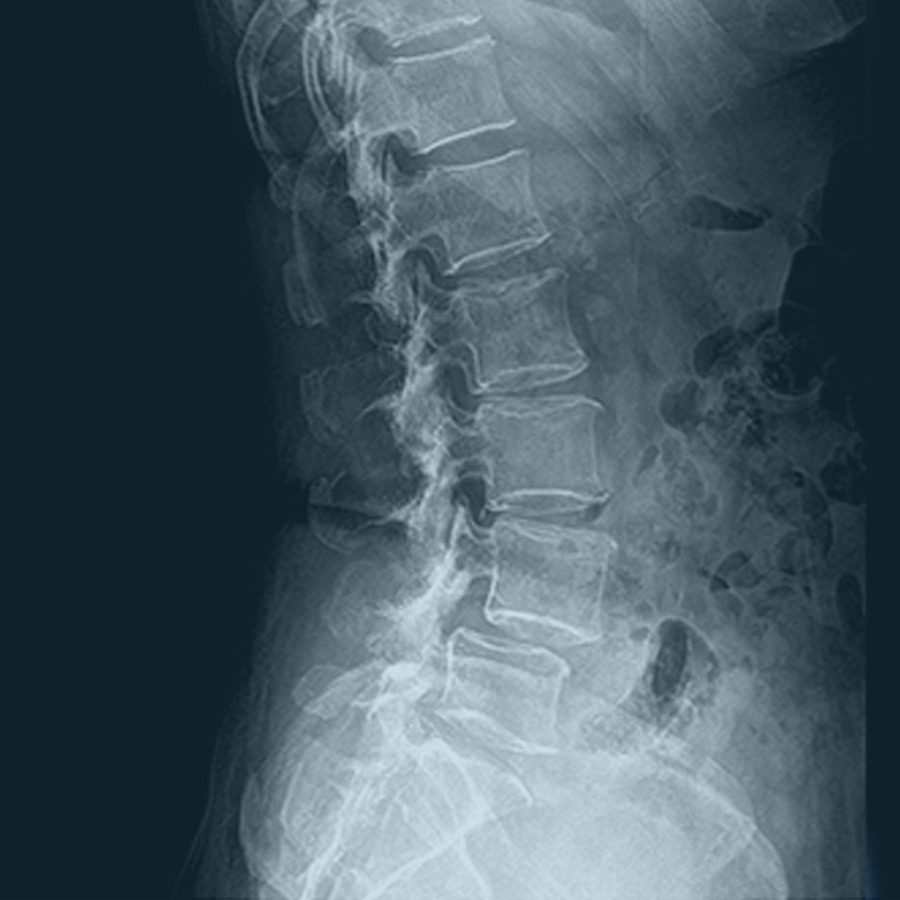

허리질환 (요추 추간판 탈출증)

LUMBAR HERNIATED INTERVERTEBRAL DISC,HIVD

척추관 협착증

SPINAL STENOSIS

척추전방전위증

SPONDYLOLISTHESIS